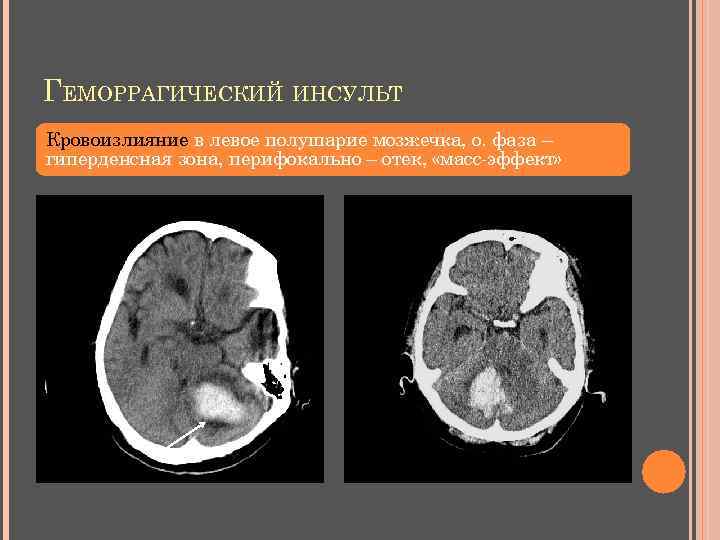

ГЕМОРРАГИЧЕСКИЙ ИНСУЛЬТ Внутримозговые ( супратенториальные, полушарные) 1. Латеральные - поражение базальных ядер, внутренней капсулы, белого вещества - поражение базальных ядер, массивное поражение белого вещества 2. Лобарные 3. Медиальные - поражение таламуса и внутренней капсулы - поражение таламуса, внутренней капсулы, среднего мозга 4. Смешанные Внутримозговые стволовые (субтенториальные) 5. Внутрижелудочковые 6. Кровоизлияния в мозжечок 7. Стволовые кровоизлияния и в III , IV желудочки Оболочечные кровоизлияния 8. Субарахноидальные 9. Субдуральные 10. Эпидуральные

ГЕМОРРАГИЧЕСКИЙ ИНСУЛЬТ Острая стадия - до 3 суток гиперденсная зона (40 -90 HU) с нечеткими контурами (свежая кровь - ↑ концентрация белка в молекуле Hb) перифокально – гиподенсная зона (отек, ишемия) КУ по периферии «–» Подострая стадия - 3 -14 дней снижение плотности от периферии к центру изоденсная зона (окисление Hb до мет-Hb) сохраняется перифокальный отек «масс-эффект» КУ по периферии «+» (формируется капсула – конец 1 -й недели) Хроническая стадия - 14 дней – 6 месяцев четко очерченная гиподенсная зона (резорбция жидкости и белка из сгустка крови → дефект мозговой ткани) КУ по периферии «+»

ГЕМОРРАГИЧЕСКИЙ ИНСУЛЬТ Кровоизлияние в левое полушарие мозжечка, о. фаза – гиперденсная зона, перифокально – отек, «масс-эффект»